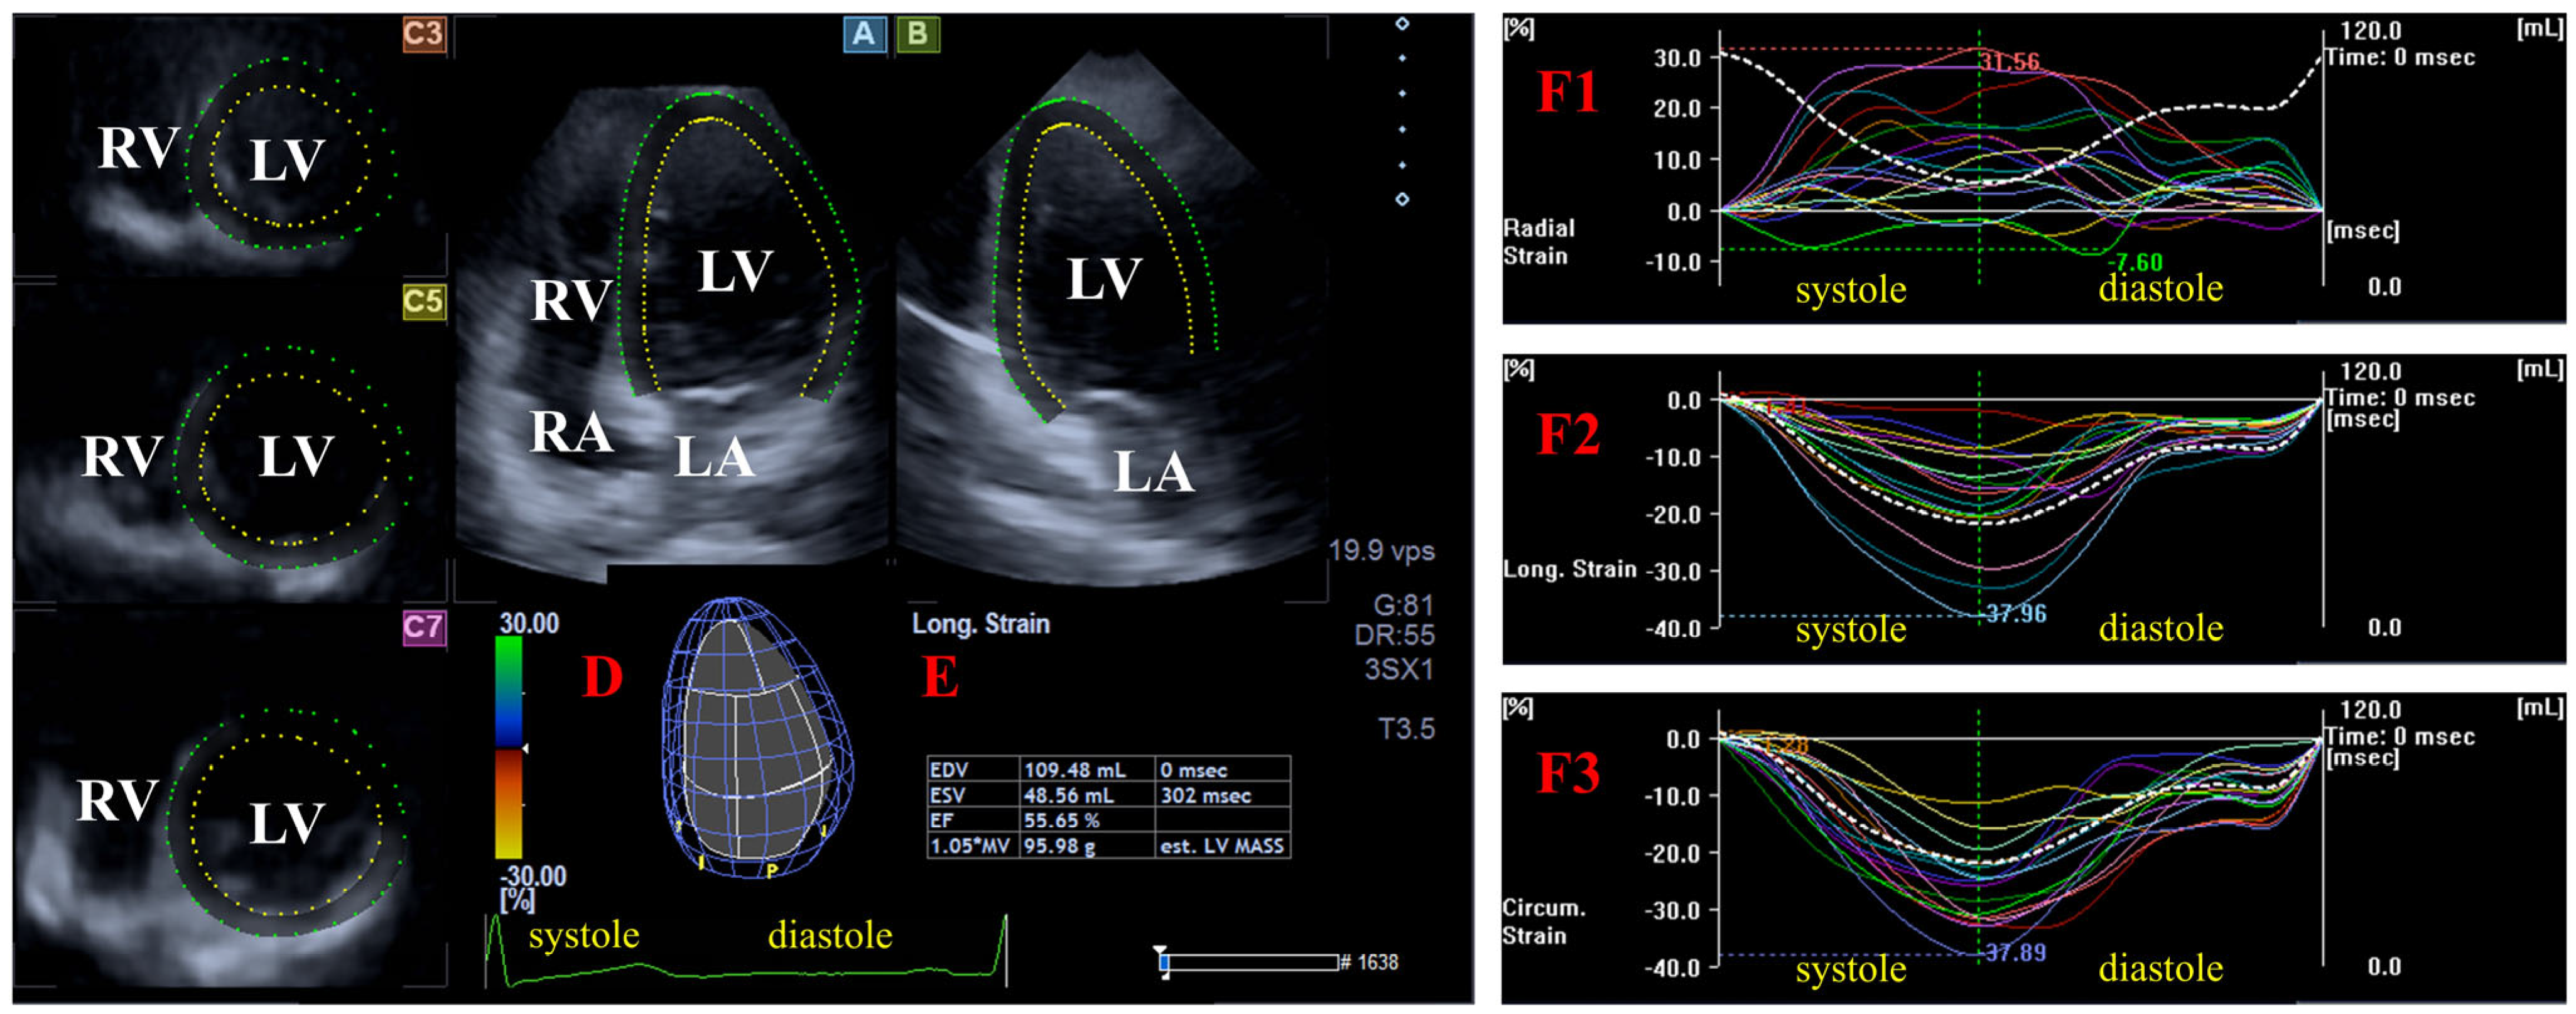

2. Materials and Methods

- Radial (RS) representing the thickening/thinning of the LV;

- Circumferential (CS) representing the narrowing/widening of the LV;

- Longitudinal strain (LS) representing the shortening/lengthening of the LV.

3. Results